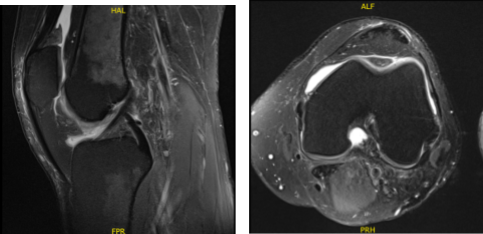

Swelling has decreased. MRI were reviewed and discussed wherein the results have shown 9 x 6 mm full-thickness chondral defect in the midportion of the medial femoral condyle. Focal area of Chondral fissuring and partial-thickness cartilage loss in the central trochlea. Intact medial and lateral meniscus.

MRI-3T Left knee non-contrast